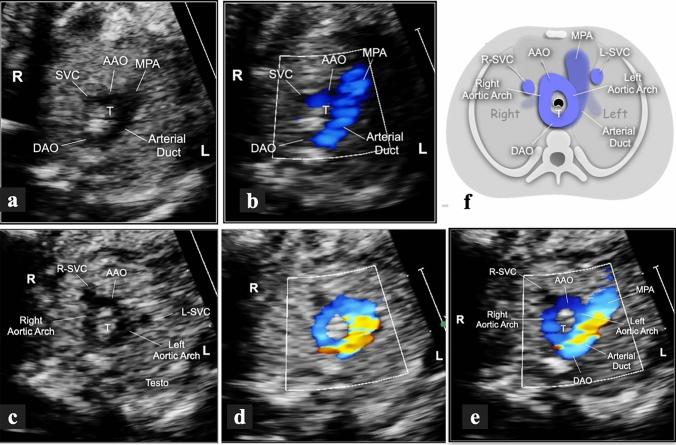

To study the different characteristics of arterial duct (AD) in a series of prenatally detected right aortic arch (RAA). Out of 832 congenital heart diseases (CHD) referred to a tertiary center, 98 cases had RAA. Based on anatomical landmarks we identified 7 types of AD: type 1 left-sided, transverse; type 2 left-sided, vertical; type 3 from the underside of aortic arch (AA), vertical; type 4 right-sided, mirror-image "V", transverse; type 5 right-sided, "H" shaped, transverse; type 6 bilateral; type 7 absent or unidentifiable. For each type of AD the incidence of associated major CHD was calculated and chi-square test was applied to verify the null hypothesis with significance level of p < 0.05. Type 1 occurred in 43% of cases including 4 with CHD and no cases with pulmonary outflow obstruction (POO). Symptoms of vascular ring were present in 41% of survivors. Type 2, 3 and 7 AD were associated with tetralogy of Fallot (TOF) or equivalents. No type 5 AD with CHD had POO and 3 isolated cases had asymptomatic hypoplasia of left pulmonary artery (LPA). Two type 6 AD had disconnection of LPA. Type 1 occurred more often as an isolated finding (p < 0.001), whereas types 2 (p = 0.0026), 3 (p = 0.0045), 4 (p = 0.0325) and 7 (p = 0.0001) were frequently associated with major CHD. In RAA, type 1 (U-shaped) is usually an isolated finding (p < 0.001) which includes all symptomatic vascular rings. POO is always present when the AD is vertical or absent but not when it lies on a transverse plane. Bilateral AD is rare and brings the risk of functionary loss of left lung if not identified.

研究一系列产前检测到的右主动脉弓(RAA)中动脉导管(AD)的不同特征。在转诊至三级中心的 832 例先天性心脏病(CHD)中,有 98 例存在 RAA。根据解剖学标志,我们确定了 7 种类型的 AD:1 型为左侧、横向;2 型为左侧、垂直;3 型为主动脉弓(AA)底部、垂直;4 型为右侧、镜像“V”形、横向;5 型为右侧、“H”形、横向;6 型为双侧;7 型为缺失或无法识别。对于每种类型的 AD,计算了相关主要 CHD 的发生率,并应用卡方检验来验证具有统计学意义的 p<0.05 的零假设。1 型发生在 43%的病例中,包括 4 例 CHD 患者和无肺流出道梗阻(POO)的患者。41%的幸存者存在血管环症状。2、3 和 7 型 AD 与法洛四联症(TOF)或等效物相关。无 CHD 的 5 型 AD 伴有 POO,3 例孤立性左肺动脉(LPA)发育不全。2 例 6 型 AD 存在 LPA 分离。1 型更常作为孤立性发现(p<0.001),而 2 型(p=0.0026)、3 型(p=0.0045)、4 型(p=0.0325)和 7 型(p=0.0001)常与主要 CHD 相关。在 RAA 中,1 型(U 形)通常为孤立性发现(p<0.001),包括所有有症状的血管环。当 AD 垂直或缺失时,POO 总是存在,但当 AD 位于横平面时则不存在。双侧 AD 罕见,如果未识别,会导致左肺功能丧失。